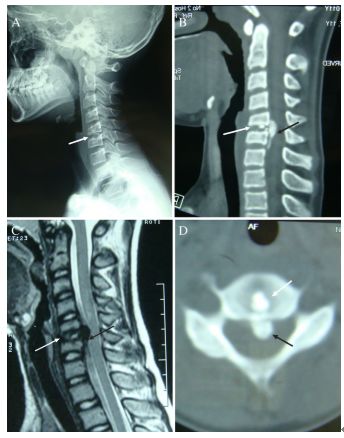

图:患者8岁,女孩,因严重颈部疼痛、活动受限伴左上肢无力、麻木不适2天就诊。既往有锁骨骨折、额部软组织挫伤病史。查体:颈椎活动受限,左上肢肌力正常,但感觉减退。白细胞、血沉、CRP升高。颈椎侧位片和CT平扫提示C6-7椎间盘钙化(粗箭头)和后纵韧带骨化(细箭头),颈椎MRI提示C6-7水平脊髓明显受压。给予颈椎制动、枕颌带2.5kg颈椎牵引2周。随后,颈托固定1个月。2年后随访复查颈椎CT如下图,同时上述症状完全缓解。

图:2年后复查CT示C6-7钙化的椎间盘和后纵韧带骨化都消失了

图:8岁女孩,因颈腰痛伴左上肢放射痛2月余就诊,颈椎侧位片、CT和MRI表现与上述病例类似。

图:给予保守对症治疗(具体不详)1月后症状消失。6个月时随访可见钙化的椎间盘和后纵韧带都消失了。